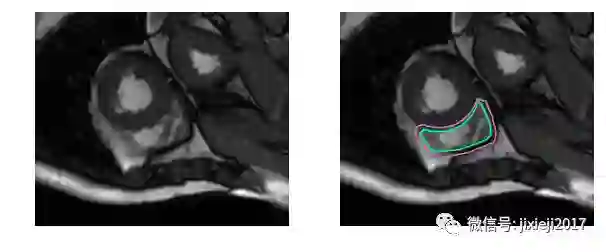

不使用医学术语,识别右心室困难的原因是:左心室是一个厚壁的圆柱型区域,而右心室是一个不规则形状的物体,较薄的心室壁有时会与周围的组织混在一起。下图是MRI快照中手工绘制的右心室内壁和外壁(心内膜和心外膜)轮廓:

上图的分割较简单。下面是一个比较困难的分割: